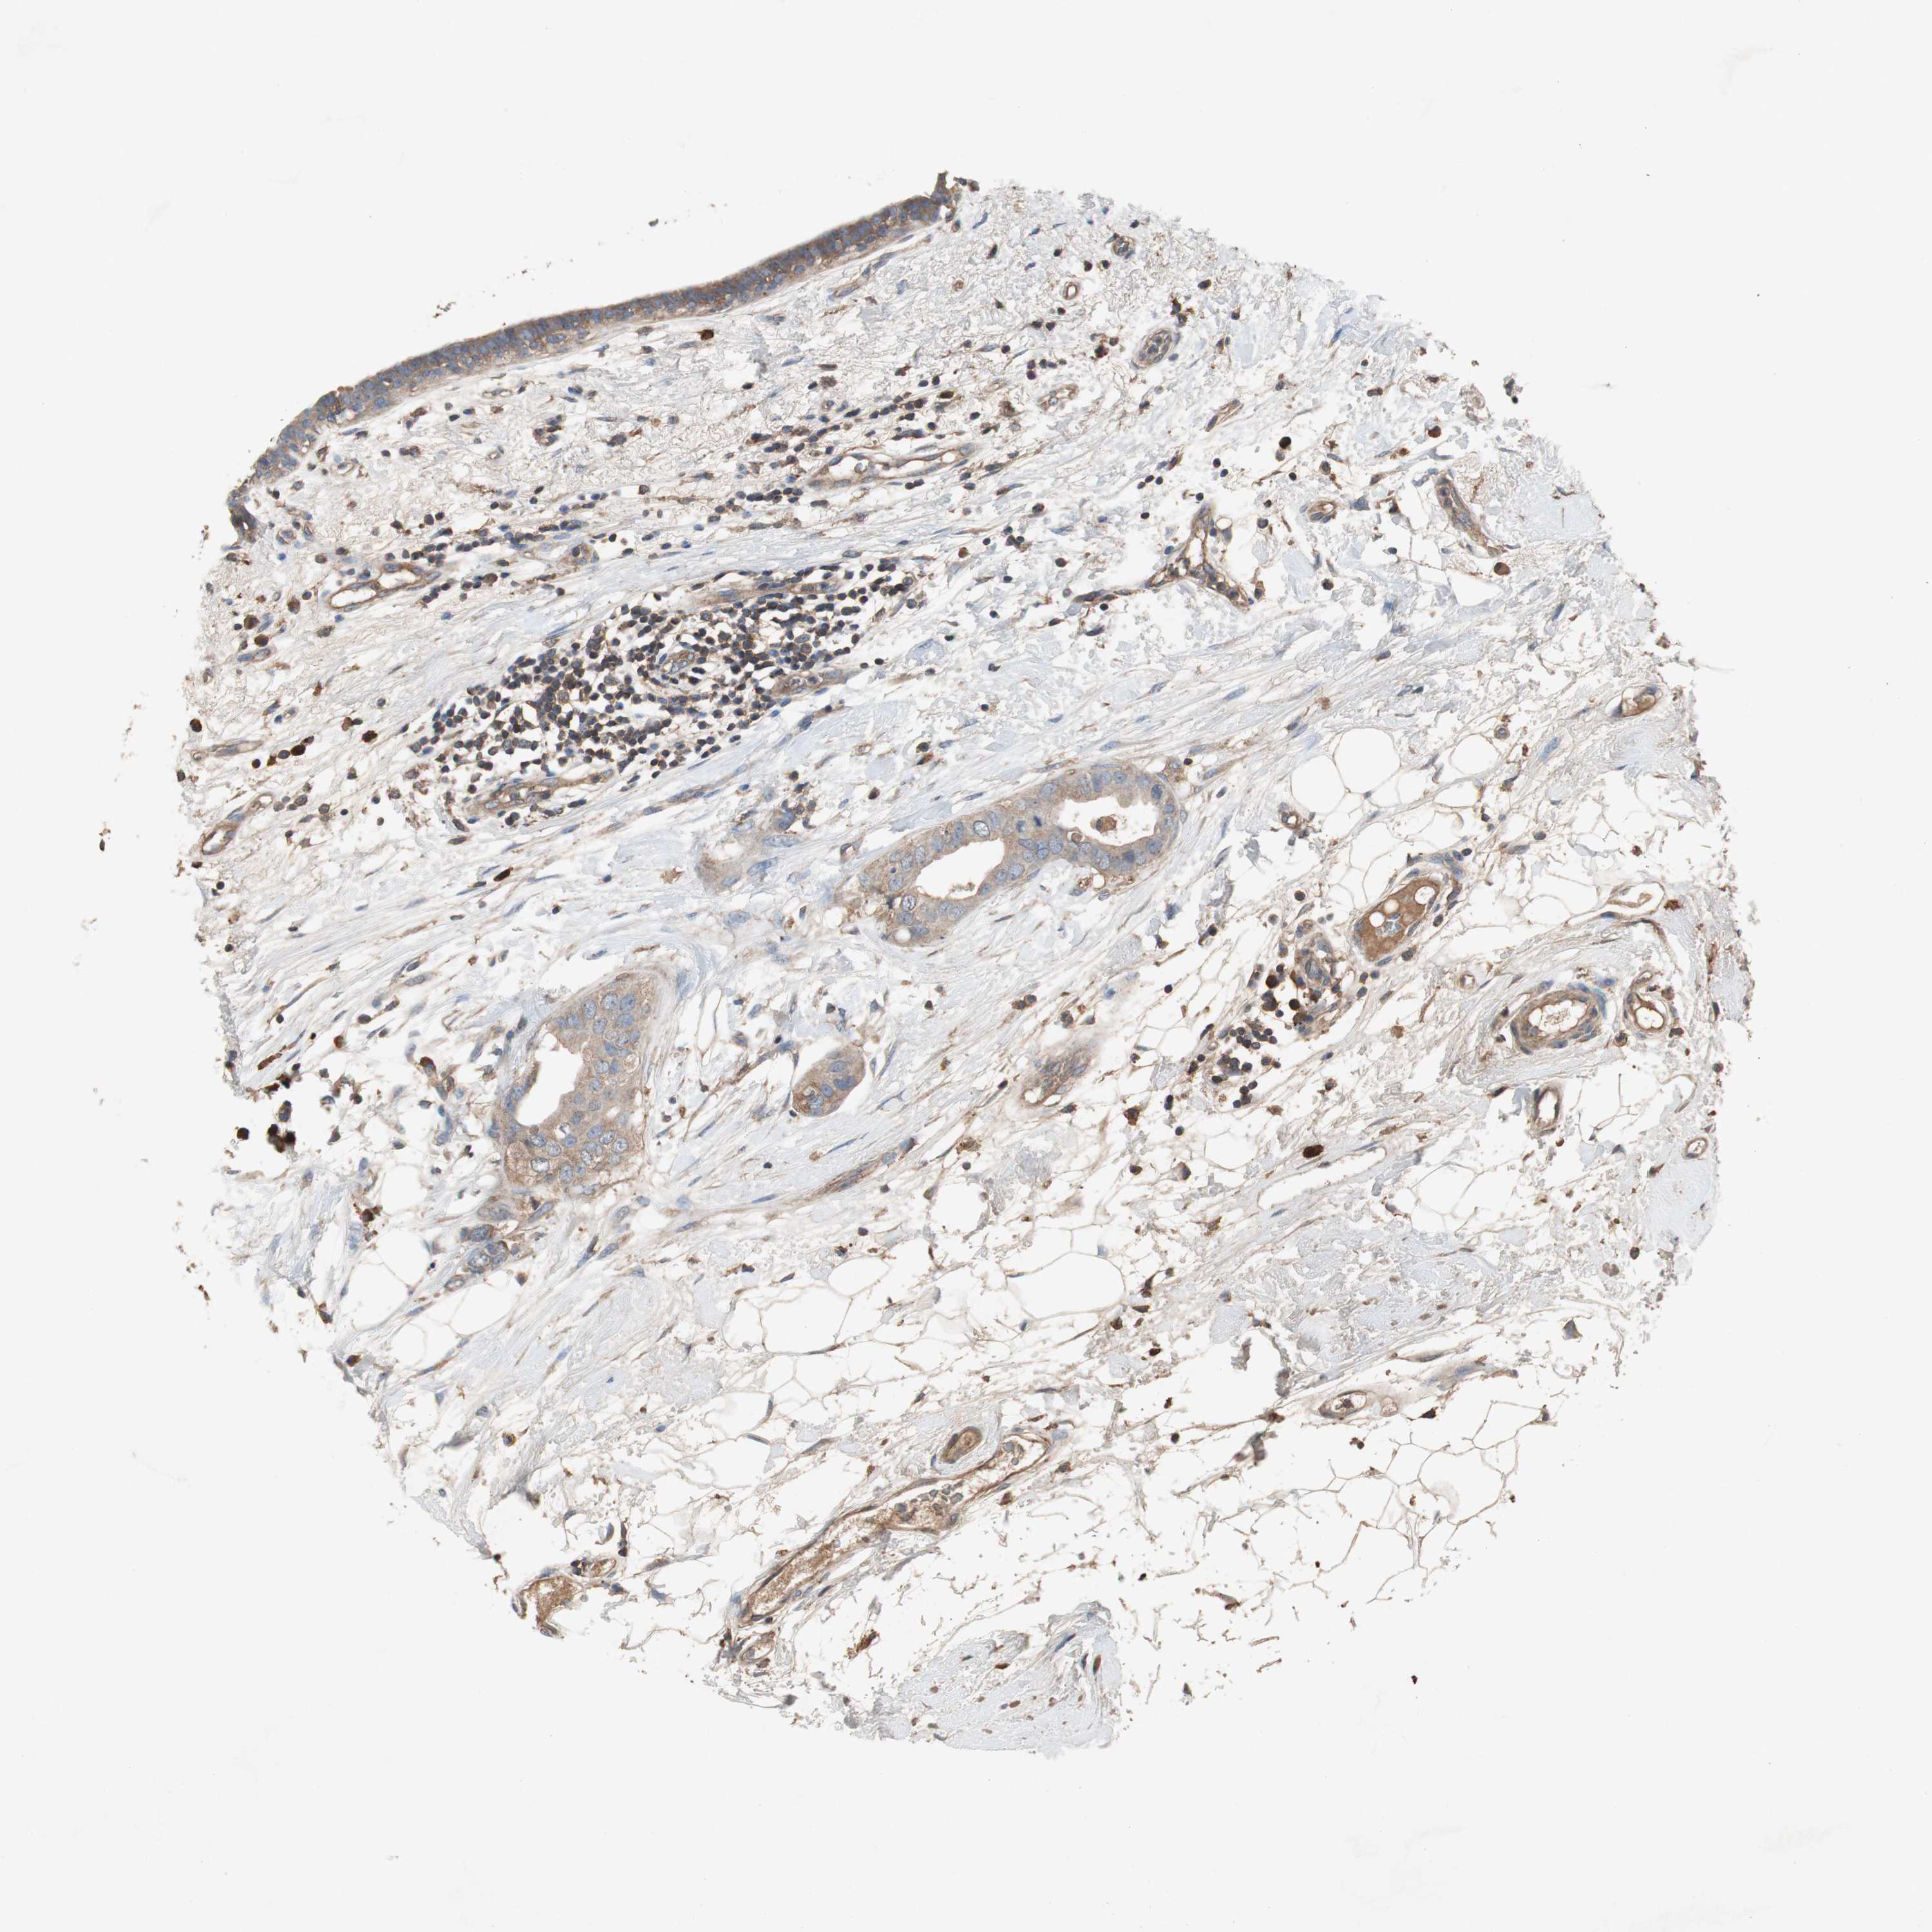

CANCER BREAST CANCER Show tissue menu

BRCA TCGA BRCA VALIDATION PROTEIN EXPRESSION